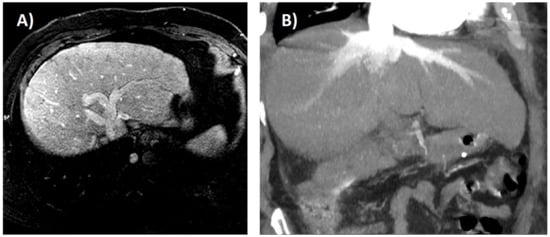

- Morales, A.; Hirsch, M.; Schneider, D.; González, D. Congestive hepatopathy: The role of the radiologist in the diagnosis. Diagn. Interv. Radiol. 2020. [Google Scholar] [CrossRef] [PubMed]

- Wells, M.L.; Venkatesh, S.K. Congestive hepatopathy. Abdom. Radiol. 2018, 43, 2037–2051. [Google Scholar] [CrossRef] [PubMed]